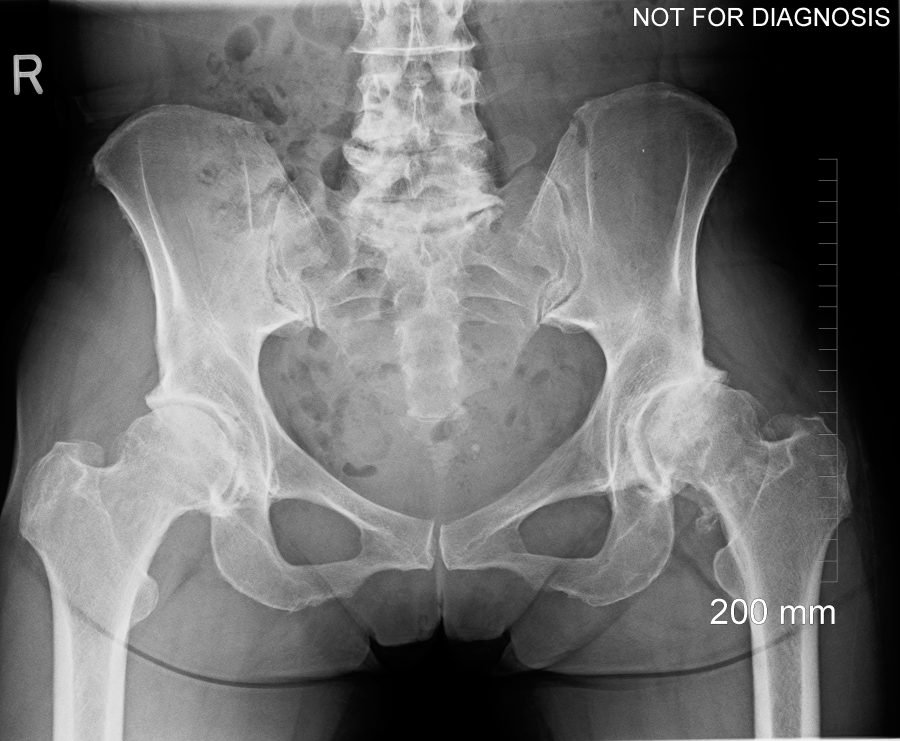

hips.jpg